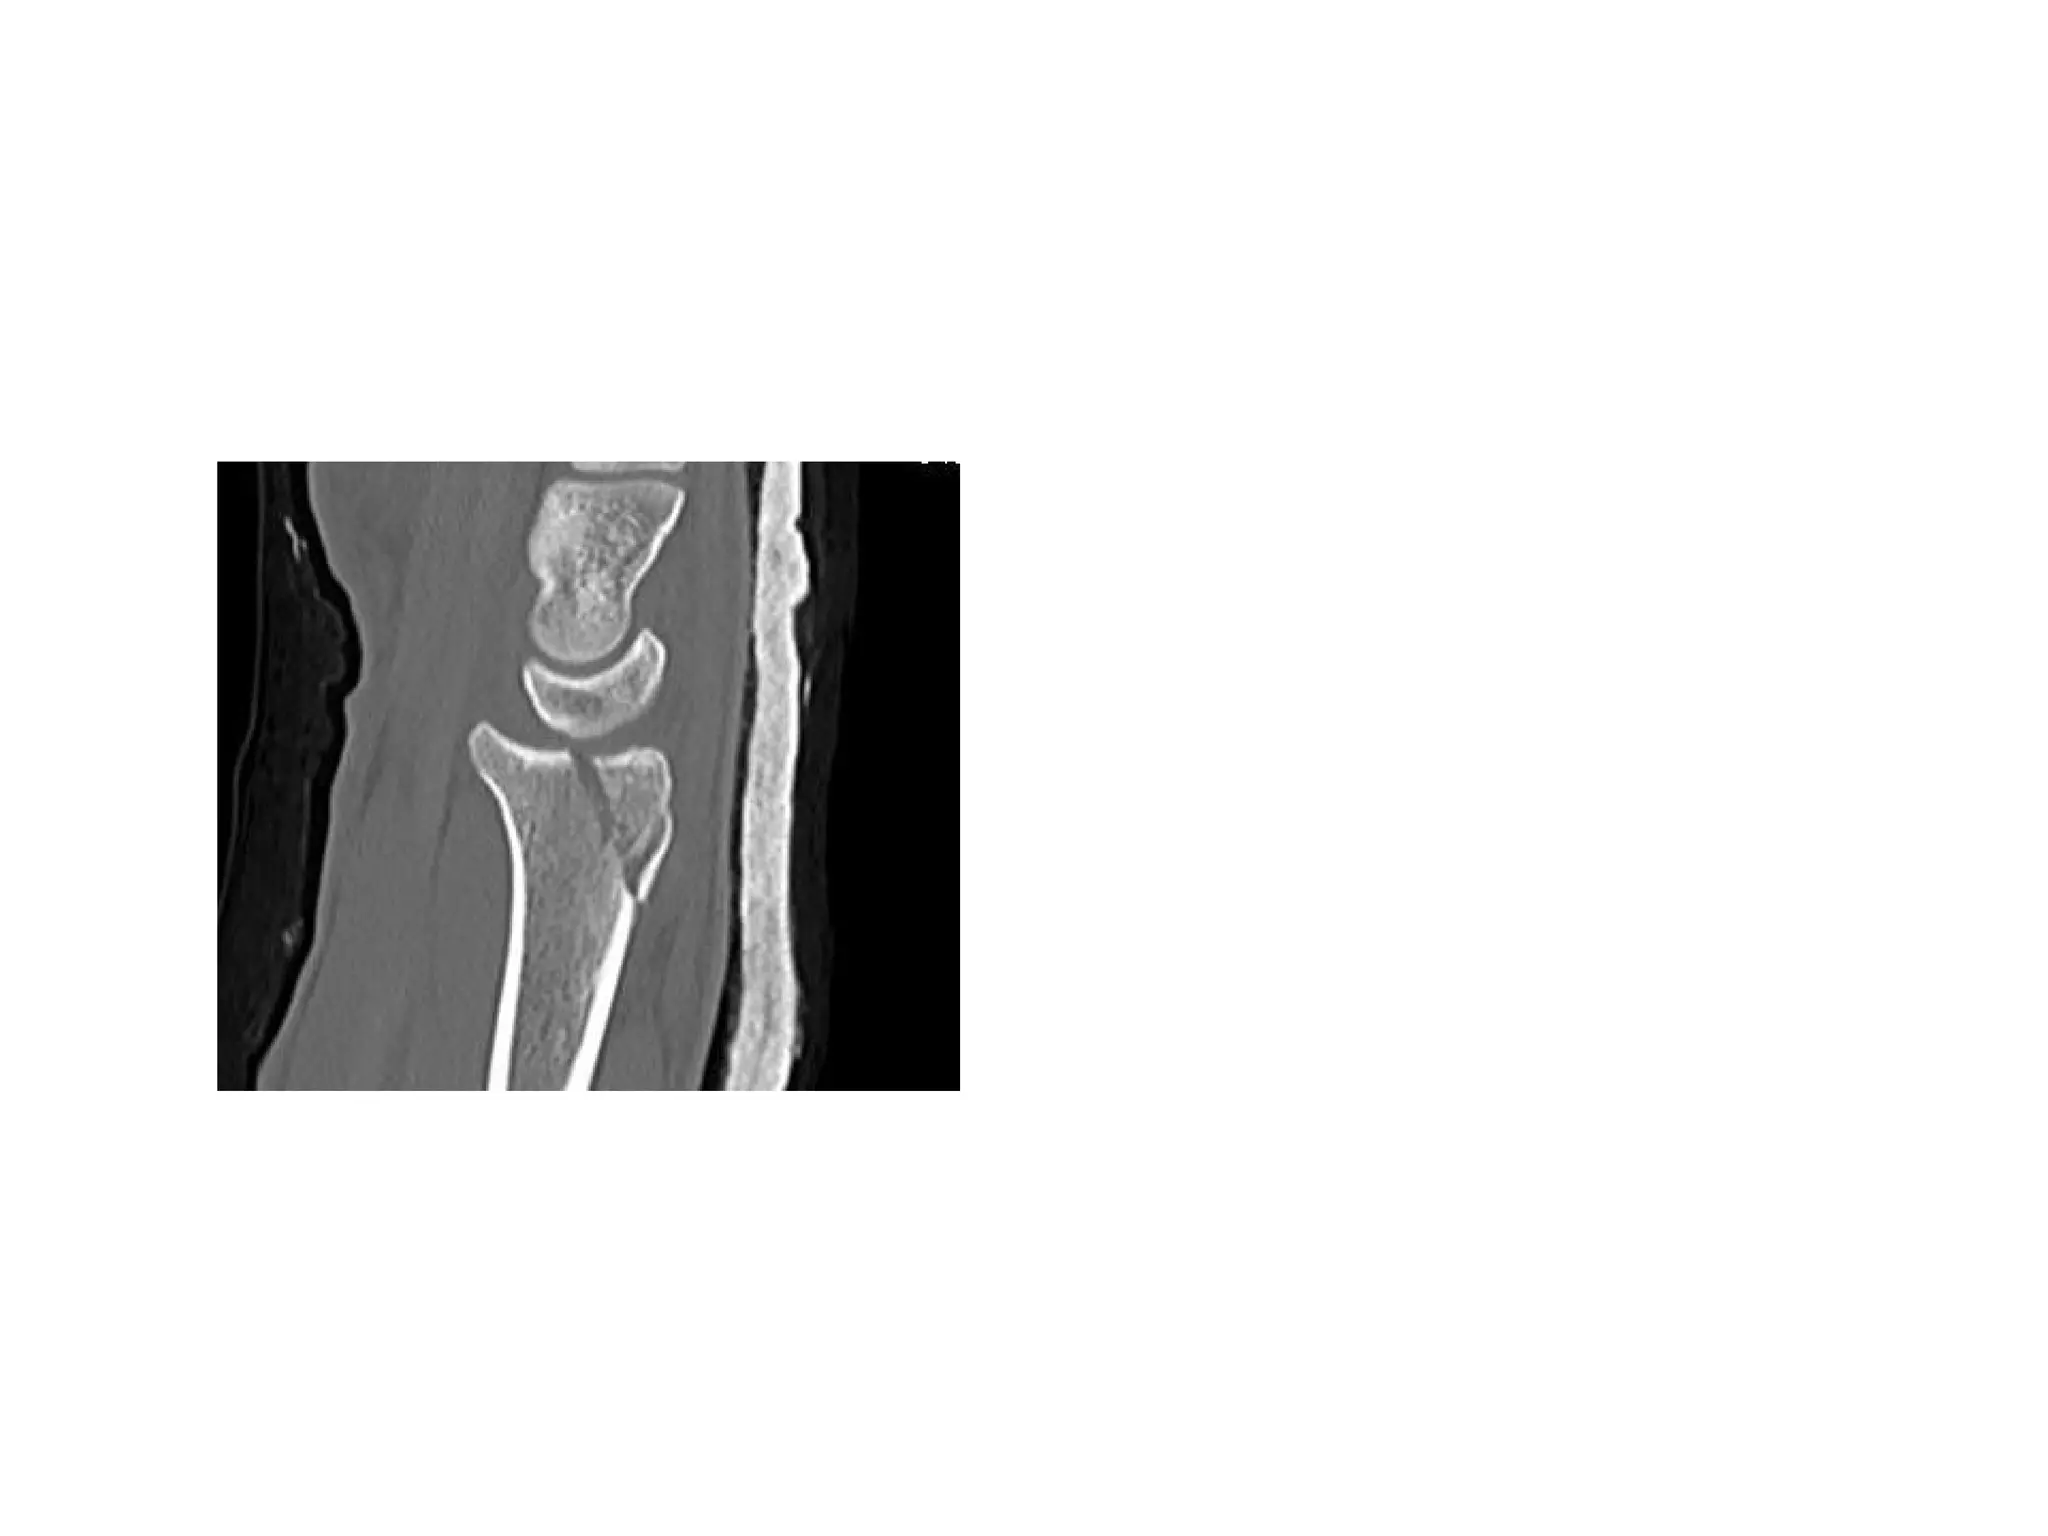

• CT Scan-for staging & if plain flims normal

• 8.

• #5 Primary blood supply is dorsal branch of radial artery -70 to 85% other is volar scaphoid branch supplies distal portion of the bone 20 to 30 %

• #9 1.PA 2.LATERAL 3.SCAPHOID VIEW…WRIST EXTENSION 30 DEGREE & ULNAR DEVIATION 20 DEGREE 4.SUPINATED OBLIQUE OTHERS PRONATED OBLIQUE

• #10 IMAGING OF CHOICE SCAPHOID VIEW ……